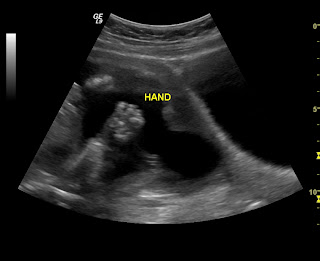

Here are some pics of our little princess!